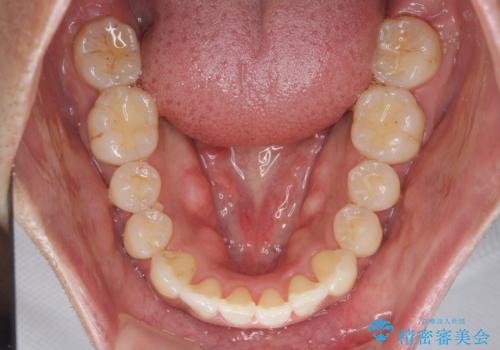

マウスピース矯正で前歯の見た目を治したい

- 前歯のガタつきをきれいにしたい、と矯正治療を希望され来院されました。

マウスピース矯正インビザラインを用いてガタつきをきれいに並べていきます。

外側に傾斜していた前歯の角度も良くなり、「前歯の見た目が良くなった。」、と喜んでいただくことができました。